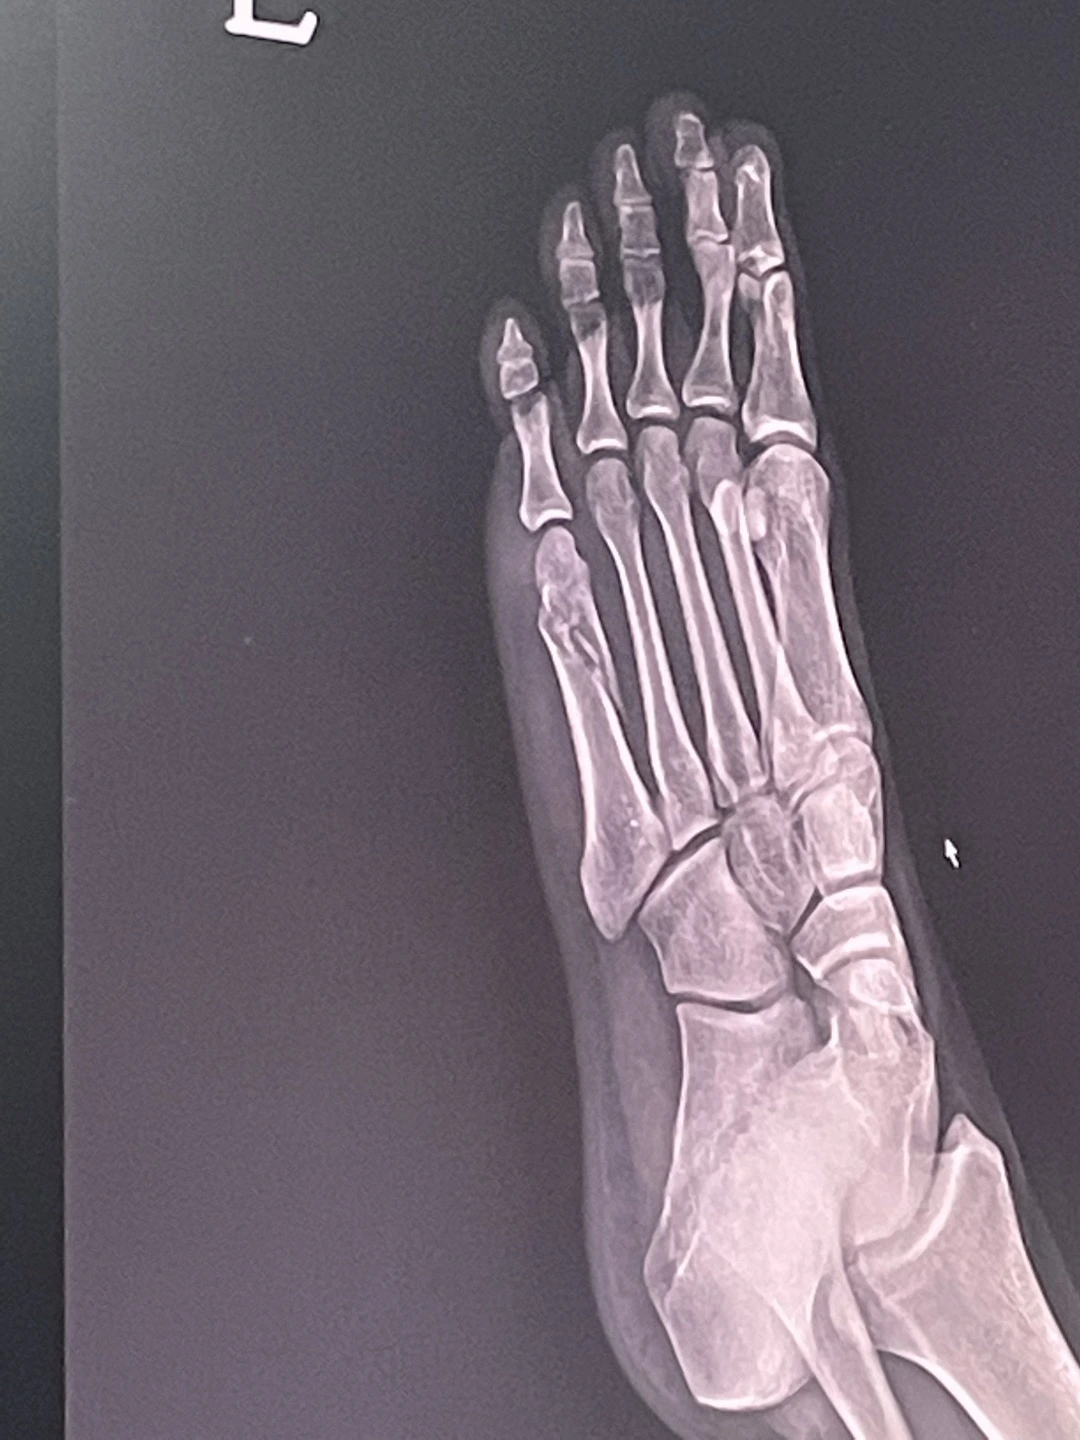

왼쪽 발목 인대가 찢어졌다. 이번으로 세 번째다. 조금이라도 키가 커 보이려 신었던 높은 깔창의 운동화가 원인이었다. 사람이 가득한 강남대로변에서 발을 접질려 고꾸라졌다. 아픔보다는 창피함이 더 커 벌떡 일어나 멀쩡한 척 걸어왔지만, 다음 날 아침 바로 알았다. 한동안 제대로 걷지 못하겠구나. 한 달 전 집 현관에서 넘어져 발등뼈가 부러졌던 룸메이트는, 우리 집에 ‘발병’이라는 전염병이 도는 게 분명하다며 자조했다.

KakaoTalk_Photo_2023-04-17-15-21-50.jpeg 룸메이트 Y의 발

깁스를 푼 지 얼마 안 된 룸메이트가 목발 짚는 법에 대해 조언해주었다. 목발을 20cm 정도 앞으로 옮기고, 딱 그만큼만 전진하라고 했다. 욕심을 내서 성큼성큼 걸으려고 했다가는 또 넘어져서 다른 곳도 부러질 수 있다며 겁을 주었다. 걷는 일이 이토록 힘겨운 일이었던가? 평소 걸음이 빠른 나는, 원래 내 속도라면 이보다 10배는 빨랐을 거라며 답답해했다. 그리고 평소엔 생각치도 못했던 이 도시의 문제를 발견했다. “그런데, 횡단보도 신호 너무 짧지 않아?”